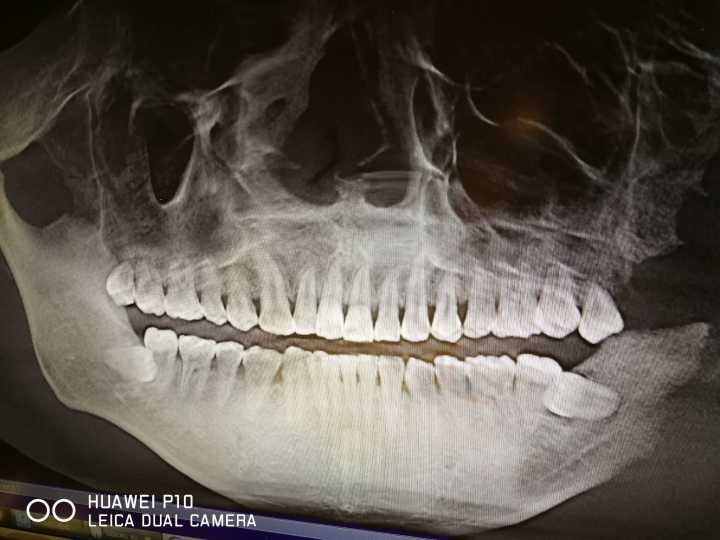

智齿的由来智齿是指人类口,牙槽骨上最里面的上下左右各一的4颗第三磨牙。因为这4颗第三磨牙正好在20岁左右时开始萌出,此时人的生理、心理发育接近成熟,于是被看做是“智慧到来”的象征,故称它为“智齿”—智慧之齿。相传古代有一位君王,少年继位,已近成年时,又长牙齿,终日疼痛难,皇帝惊怪,问臣主吉主凶。其中有一位溜须拍马之臣奏曰:“此乃智人之相也。”皇帝大喜,并赐金高升。这可能就是古代“智齿”名称之由来。其实,从现代医学的观点看,智齿是人类进化的必然。众所周知,“用进废退”是生物进化论中的一个普遍规律。智齿就是极好的例证。

人类的恒牙列共有三十二颗牙,其中**萌出的四颗第三大臼齿,位于上下左右牙弓的**方,因为萌出在智能成长后十六到廿四岁,所以又有智能齿之称,简称智齿。

然而,由于演化及食物精化,人类的颌骨,因为不再需要强大的咀嚼力而有逐渐变小的趋势,在这变小的颌骨上如要容纳跟以往相同数目及大小的牙齿,则牙跟牙之间往往会有空间不足的问题,于是拥挤,长倒,长弯,或长不出来的情形便发生,这就是阻生。就统计上而言,长不出来的情形最常发生在智齿,所以习惯上常称这种长不出来的智齿为阻生智齿。良生不建议拔智齿。

在临床上看起来,大多数的人应该都有智齿,所以可以自己照镜子看看由中线算起的上下左右是不是都有第八颗牙?长的好不好?正不正?是不是常常会发炎疼痛?而且算完之后,不管有没有第八颗牙,在定期检查时都应请牙确认一下,如果是天生缺牙时倒还值得庆贺,因为一切没事,如果不幸发生了长不出来的情形,那只好请牙尽早将它拔除,因为长不出来的智齿位于口腔**方不易清洁的位置,残留的食物残渣容易被细菌所利用来人体。

在平时,细菌造成的慢性感染会使牙龈发炎,容易,骨吸收,蛀牙及牙痛,**因的或牙髓坏死而拔牙,这时隔壁有用的第二大臼齿往往也会受到波及而造成不等程度的伤害,甚至拔牙,这也是最可惜的地方。在身体疲累虚弱或重病时,细菌引起的急性发炎反应更是厉害,轻者造成智齿周边红热肿胀,疼痛不堪,张口、吞咽、咀嚼困难及淋巴腺肿等等,重者引起大范围感染肿胀之蜂窝织炎,化脓性肿胀及发烧恶寒等全身性症状,如未予以适当处置(***及切开引流手术),甚至会有致命危险。老人说长智齿命好。

此外智齿若长不出来,残余的牙胚有可能会而形成口腔肿瘤。空间不足时其牙胚可能会吸收前方第二大臼齿之牙根使强度减低,影响其功能。异位或萌出不全的智齿亦往往会对正常咬合造成干扰,牵动下颌骨之必须常常作出异常收缩来避开此一干扰而使得及关节容易有发炎疼痛之现象。

虽说智齿长不出来有可能带来以上之种种问题,但它最早通常都是以牙冠周围发炎疼痛的症状被发现,此时不要害怕,应该痛下决心,听从牙的指示,按时服药,忍痛刷牙,务必清洁干净以利复原,一旦牙冠周围炎之症状解除,立刻安排拔牙,才可永除后患。

智齿牙位不正常,与邻牙形成间隙者;智齿牙位虽正常,但智齿牙冠有骨或牙龈瓣覆盖,经常发生冠周软发炎、肿胀、疼痛者;智齿已龋坏,或发生牙髓炎,又不便进行牙体牙髓**者;因正畸需要,如预防后牙向前移动和防止前牙拥挤加重者,均可考虑拔除。

智齿的位置比较正,预计能正常萌出者;智齿冠周软没有发炎和疼痛史,智齿没有龋坏者;有对牙合牙齿并有咬合关系者;通过龈瓣切除可消除盲袋者,应考虑保留该智齿